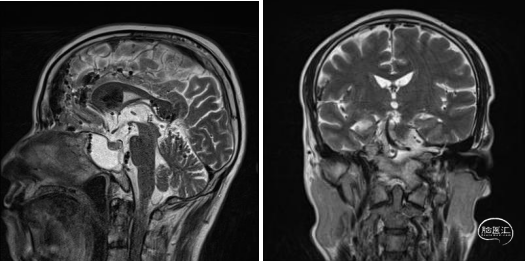

头颅磁共振T2冠矢状位平扫提示积液主要位于蝶窦腔内,筛窦及上颌窦相对干净,且未见明显占位征像。

腰穿注入造影剂行脑池造影,嘱患者俯卧,使脑脊液鼻漏持续流出。显示随着造影剂的弥散,蛛网膜下腔及蝶窦内液体逐步显影,而其他窦腔内未见造影剂显影。

至此,我们基本可以判断,漏口位于蝶窦腔内,而且斜坡骨质缺损处嫌疑最大。那实行了神经内镜下探查+脑脊液漏修补术。